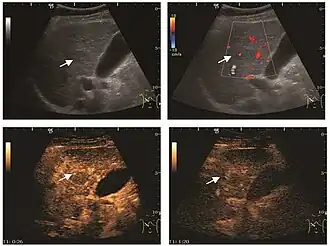

Peripheral vascular pattern of the lesion is observed in colon cancer metastasis (CEUS).

Lesion hyperenhancement in ovarian cancer liver metastasis is seen during the arterial phase.

US examination is required to detect liver metastases in patients with oncologic history. In addition, the method can incidentally detect metastases in asymptomatic patients. Early identification (small sizes, small number) is important to establish an optimal course of treatment which can be complex (chemotherapy, radiofrequency ablation, surgical resection) but welcomed. In addition, discrimination of synchronous lesions that have a different nature is also important knowing that up to 25–50% of liver lesions less than 2 cm detected in cancer patients may be benign . US sensitivity for metastases detection varies depending on the examiner's experience and the equipment used and ranges between 40 and 80% . Sensitivity is conditioned by the size and acoustic impedance of the nodules. For a lesion diameter below 10 mm US accuracy is greatly reduced, reaching approx. 20%. Other elements contributing to lower US performance are: excessive obesity, fatty liver disease, hypomobility of the diaphragm, and certain patterns of hyperechoic or isoechoic metastases that can be overlooked or can mimic benign conditions. Conventional US appearance of metastases is uncharacteristic, consisting of circumscribed lesions, with clear, imprecise or "halo" delineation, with homogeneous or heterogeneous echo pattern. They can be single (often liver metastases from colonic neoplasm) or multiple. Echogenity is variable. When increased, they can compress the bile ducts (which may be dilated) and the liver vessels. Liver involvement can be segmental, lobar or generalized. In this situation a pronounced hepatomegaly occurs. Generally, metastases have non-characteristic Doppler vascular pattern, with few exceptions (carcinoid metastases). Cyst-adenocarcinoma metastases due to semifluid content may have a transonic appearance. When increasing, they can result in central necrosis. CEUS examination is a real breakthrough for detection and characterization of liver metastases.

Increased performance is based on identifying specific vascular patterns during the arterial phase and seeing metastases in contrast to normal liver parenchyma during the sinusoidal phase. CEUS increased accuracy is due to the different behavior of normal liver parenchyma (captures CA in Kuppfer cells) against tumor parenchyma (does not contain Kuppfer cells, therefore CEUS appearance is hypoechoic). To this adds the particularities of intratumoral circulation represented by a reduced arterial bed compared to that of the surrounding normal liver and the absence of the portal vessels . In terms of vascularity, metastases can be hypovascular (in gastric, colonic, pancreatic or ovarian adenocarcinomas) with hypoechoic pattern during arterial phase, and similar during portal venous and late phases, respectively hypervascular (neuroendocrine tumors, malignant melanoma, sarcomas, renal, breast or thyroid tumors) with hyperechoic appearance during arterial phase, with washout during the portal venous phase and hypoechoic pattern 30 seconds after injection.